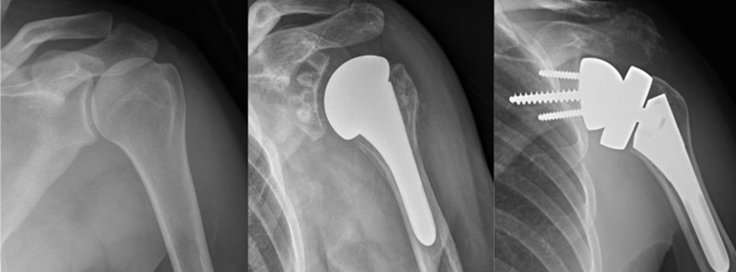

1. Total Shoulder Replacement – Replaces both the ball (humeral head) and socket (glenoid).

2. Partial Shoulder Replacement – Only the humeral head is replaced.

3. Reverse Shoulder Replacement – Used for rotator cuff tear arthropathy, where the ball and socket positions are reversed.

• The damaged bone and cartilage are removed.

• A shoulder implant is placed to restore joint function.